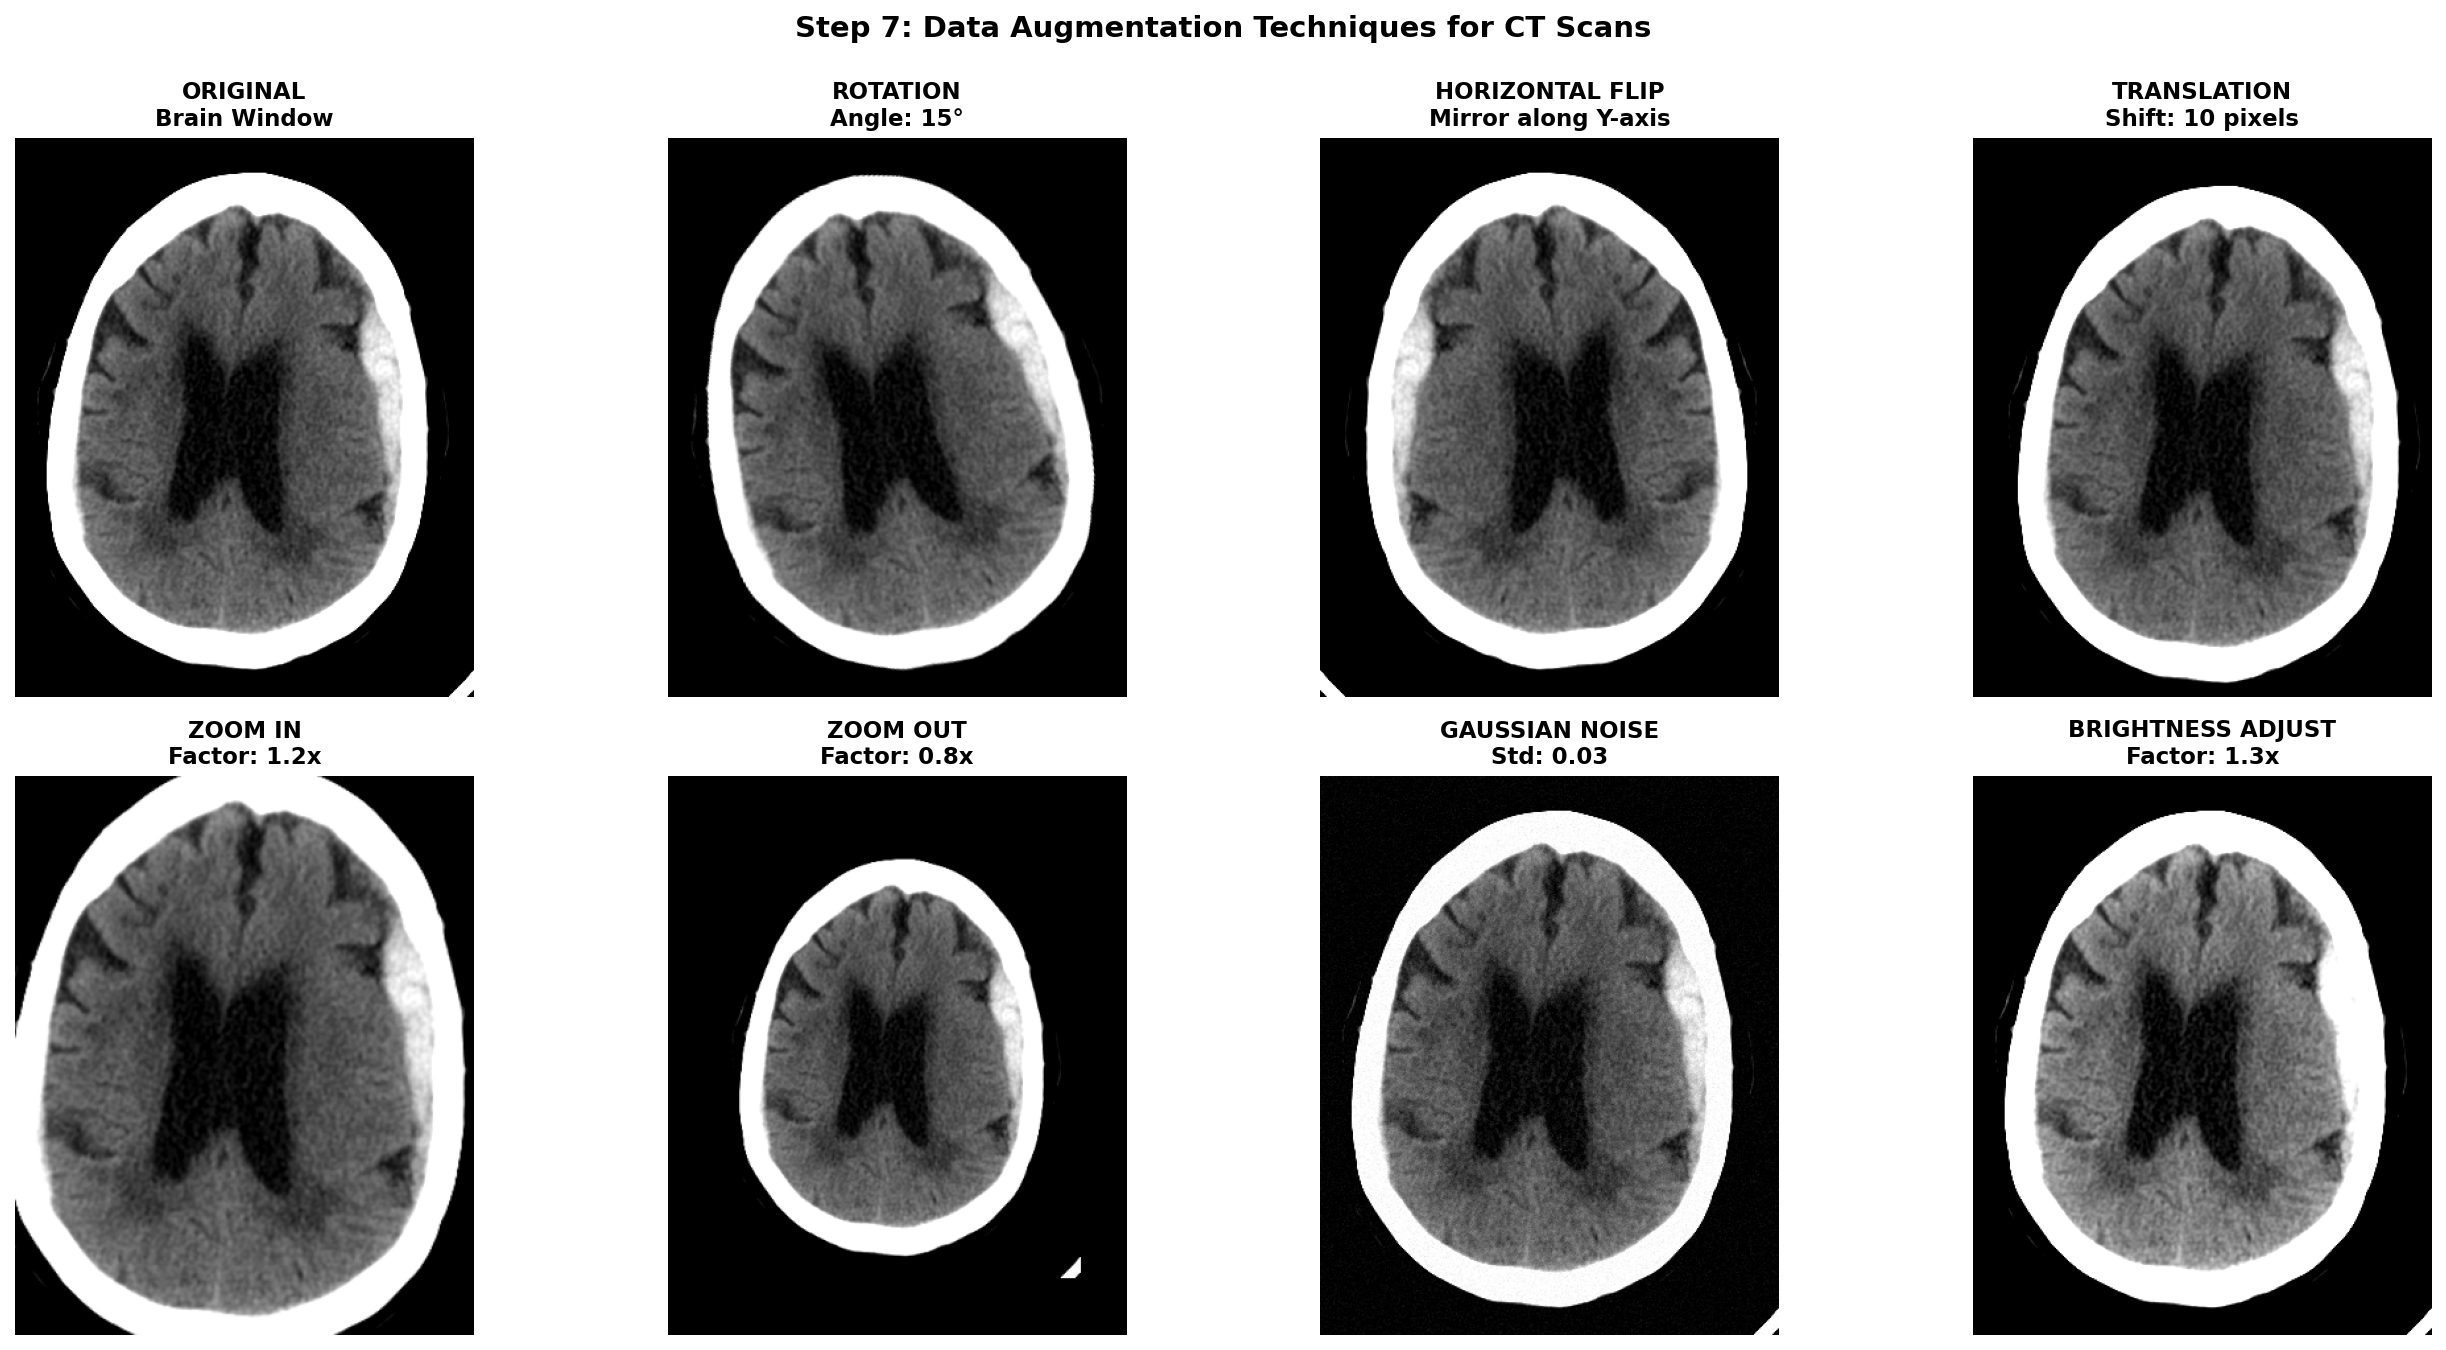

6) Data augmentation techniques for CT scans

Once all the previous preprocessing steps are complete, data augmentation becomes a powerful tool to artificially increase the size and diversity of your training dataset. This is especially crucial in medical imaging where datasets are often small, expensive to acquire, and imbalanced between normal and pathological cases. However, unlike natural images where aggressive augmentations are common, medical images require careful consideration to maintain clinical validity and avoid creating anatomically impossible or diagnostically misleading examples.

The golden rule for medical image augmentation is that transformed images must remain clinically plausible. A brain CT scan can be horizontally flipped because stroke pathology can occur on either hemisphere, but vertical flipping would be nonsensical. Similarly, slight rotations account for patient positioning variations, but extreme rotations would create unrealistic orientations never seen in clinical practice.

Augmentations are meant to simulate natural variations in patient positioning, scanner differences, and acquisition protocols. Horizontal flipping mirrors the image left-to-right which can be applied for stroke detection because a stroke can be present in both hemispheres while maintaining anatomical validity. Translations can account for slight positioning variations but it can also remove a part of the brain tissues. Small Rotations can also improve robustness by simulating patient positioning differences during exam acquisition but it shifts the pixel from the original grid and thus requires interpolation. Affine transformations can simulate slight scaling or shearing due to different head sizes or scanner distortions but should be kept minimal to avoid unrealistic deformations. Intensity transformations can also be useful to simulate light scanner noise: adding Gaussian noise, and applying slight brightness contrast adjustments by stretching or shifting the intensity values.

To implement these augmentations, MONAI is a great library specifically designed for medical imaging that provides a wide range of 2D and 3D augmentations with support for both images and segmentation masks. Transformation function can be found in the module monai.transforms with for example RandFlip, RandRotate, RandAffine, RandGaussianNoise, and RandAdjustContrast corresponding to the augmentations described above.

Notice that spatial transforms must be applied to both the image and mask with identical parameters, while intensity transforms are only applied to the image since masks contain discrete labels that shouldn't be interpolated or have noise added.

This should go without saying, but augmentation should only be applied during training. Validation and test sets must use the original, unaugmented images to provide honest performance estimates. The validation transforms should only include necessary preprocessing steps (HU conversion, resampling, windowing).

To help visualize the effect of augmentations, here are some examples applied to our hemorrhagic stroke case: